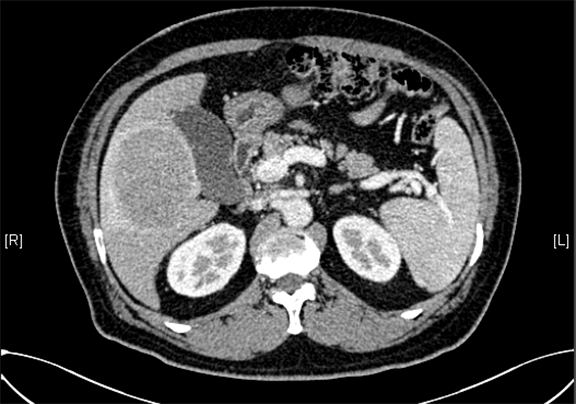

下腹部增强CT示:肝右叶恶性肿瘤可能性大;肝内多发小囊肿;肝硬化,食管胃底静脉曲张可能性大;脾脏囊肿可能性大。

术前CT检查:

动脉期

静脉期

平衡期